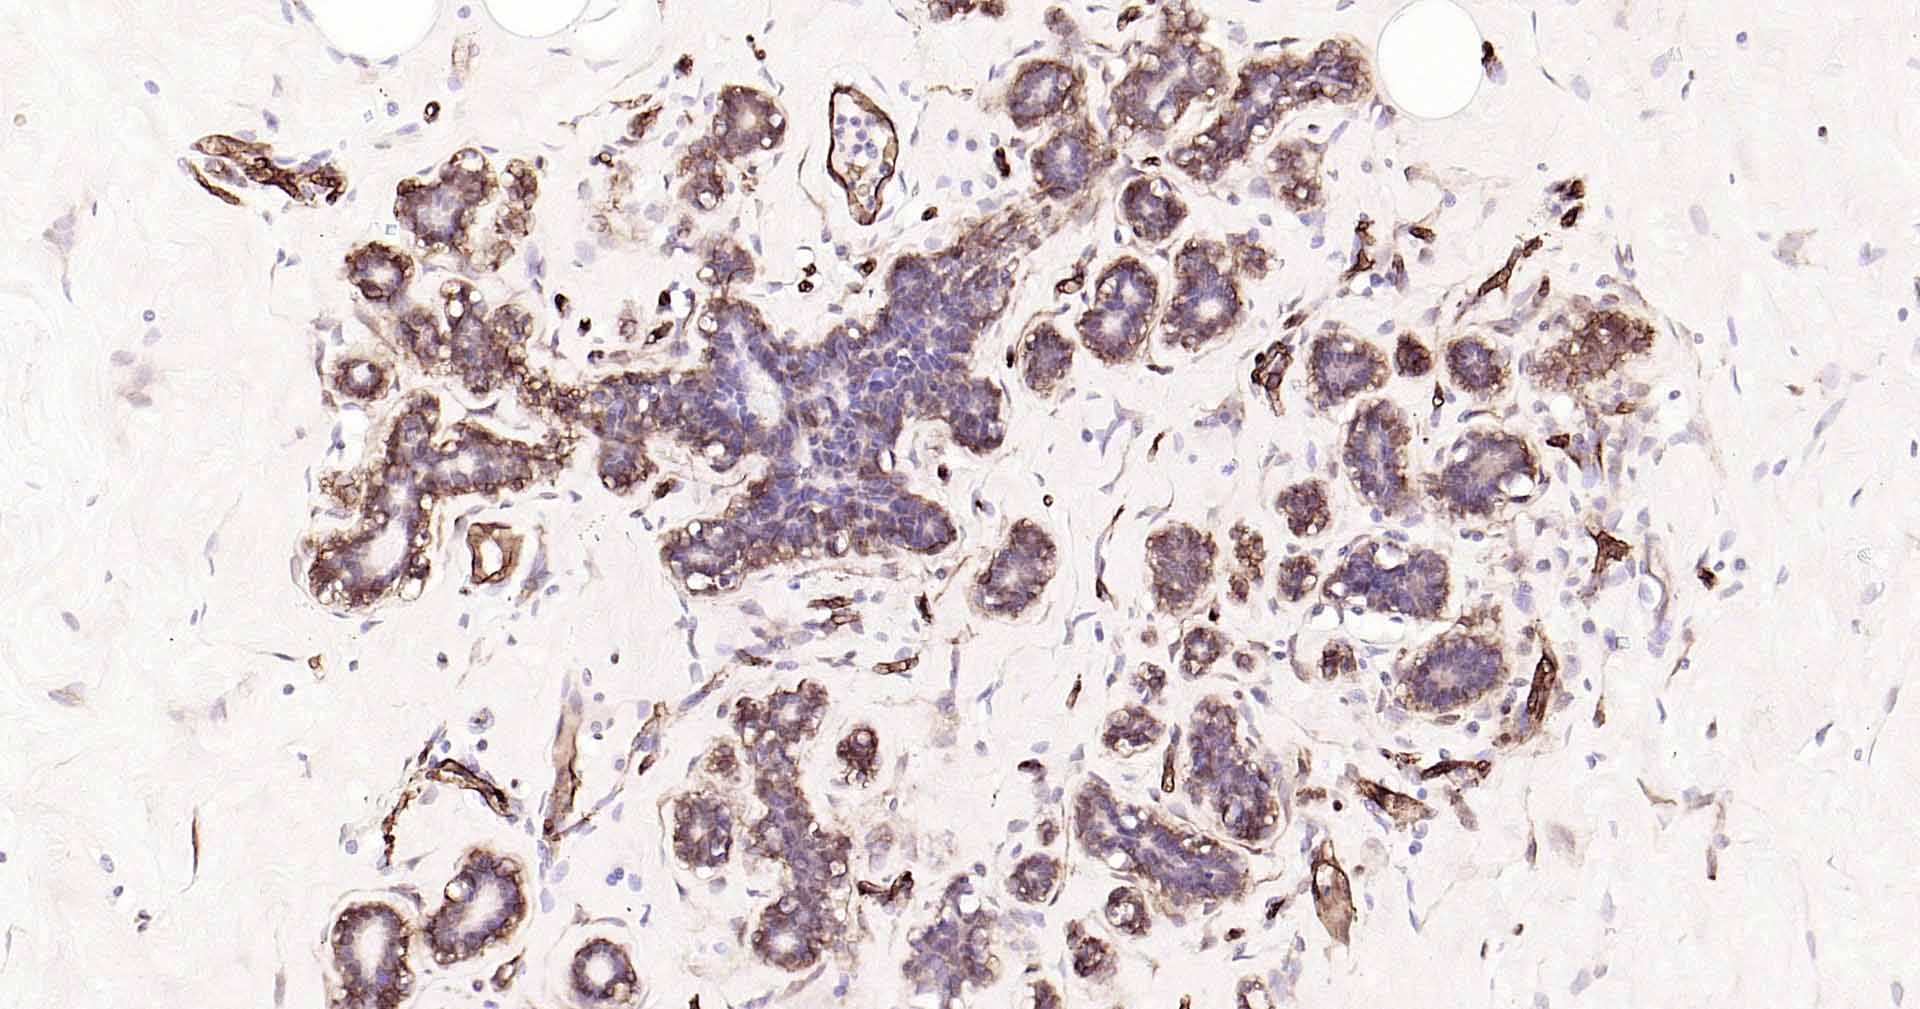

Paraformaldehyde-fixed, paraffin embedded Human Breast Cancer; Antigen retrieval by boiling in sodium citrate buffer (pH6.0) for 15 min; Antibody incubation with AQP1 Monoclonal Antibody, Unconjugated(bsm-52909R) at 1:200 overnight at 4°C, followed by conjugation to the SP Kit(Rabbit, SP-0023) and DAB (C-0010) staining.

Paraformaldehyde-fixed, paraffin embedded Human Breast ; Antigen retrieval by boiling in sodium citrate buffer (pH6.0) for 15 min; Antibody incubation with AQP1 Monoclonal Antibody, Unconjugated(bsm-52909R) at 1:200 overnight at 4°C, followed by conjugation to the SP Kit(Rabbit, SP-0023) and DAB (C-0010) staining.

Paraformaldehyde-fixed, paraffin embedded Human Colon Cancer; Antigen retrieval by boiling in sodium citrate buffer (pH6.0) for 15 min; Antibody incubation with AQP1 Monoclonal Antibody, Unconjugated(bsm-52909R) at 1:200 overnight at 4°C, followed by conjugation to the SP Kit(Rabbit, SP-0023) and DAB (C-0010) staining.

Paraformaldehyde-fixed, paraffin embedded Human Cervical Cancer; Antigen retrieval by boiling in sodium citrate buffer (pH6.0) for 15 min; Antibody incubation with AQP1 Monoclonal Antibody, Unconjugated(bsm-52909R) at 1:200 overnight at 4°C, followed by conjugation to the SP Kit(Rabbit, SP-0023) and DAB (C-0010) staining.

Paraformaldehyde-fixed, paraffin embedded Human Pancreatic Cancer; Antigen retrieval by boiling in sodium citrate buffer (pH6.0) for 15 min; Antibody incubation with AQP1 Monoclonal Antibody, Unconjugated(bsm-52909R) at 1:200 overnight at 4°C, followed by conjugation to the SP Kit(Rabbit, SP-0023) and DAB (C-0010) staining.

Paraformaldehyde-fixed, paraffin embedded Human Lung Cancer; Antigen retrieval by boiling in sodium citrate buffer (pH6.0) for 15 min; Antibody incubation with AQP1 Monoclonal Antibody, Unconjugated(bsm-52909R) at 1:200 overnight at 4°C, followed by conjugation to the SP Kit(Rabbit, SP-0023) and DAB (C-0010) staining.